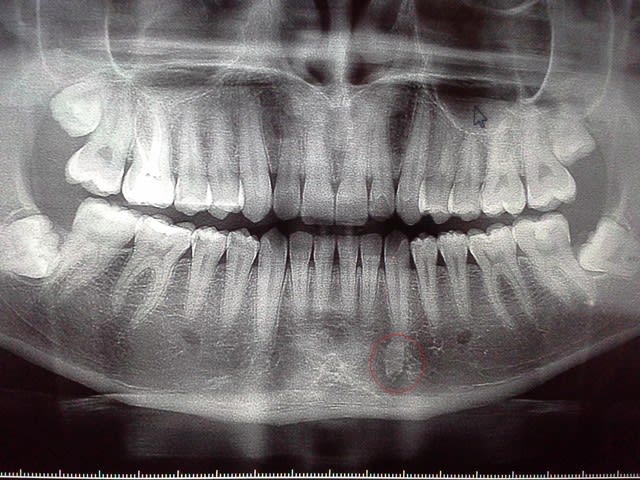

Je viens vers vous avec la pano suivante :

- Pouvez-vous me dire ce qu'est cette radio opacité au niveau de la 33 ? je pense à un odontome , Faut s'inquiéter?

- Et concernant la 48 et 38 extraction ou pas?

Donc c'est un odontome ?

=> non, odontome péri-apical, ça n'existe pas à ma connaissance. ostéocondensation banale.

> Pour la 38, avec cette morphologie radiculaire et le nerf alvéolaire qui est

> visiblement très proche , vaut mieux laisser s'il n'y a pas de symptômes non?

=> oui et non. l'expérience montre que avec le temps ce type de dent présente un jour des symptômes. faut juste expliquer au patient

> Cone beam ?

=> oui car ça te permettra de mieux comprendre ce qu'est la lésion condensante. et 2. montrer au patient la proximité avec le canal. ça ne changera rien au risque de lésion neuro ou de la manière d'opérer. c'est à titre pédagogique peut-on dire.

après le risque neuro est théorique ici.